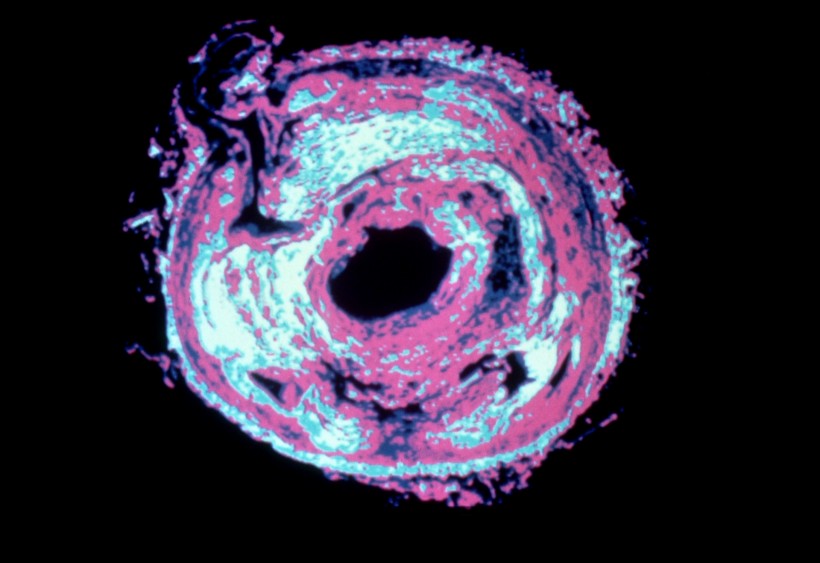

X射线是一种波长很短的电磁辐射,其波长约为(20~0.06)×10-8厘米之间。伦琴射线具有很高的穿透本领,能透过许多对可见光不透明的物质,如墨纸、木料等。这种肉眼看不见的射线可以使很多固体材料发生可见的荧光,使照相底片感光以及空气电离等效应,波长越短的X射线能量越大,叫做硬X射线,波长长的X射线能量较低,称为软X射线。